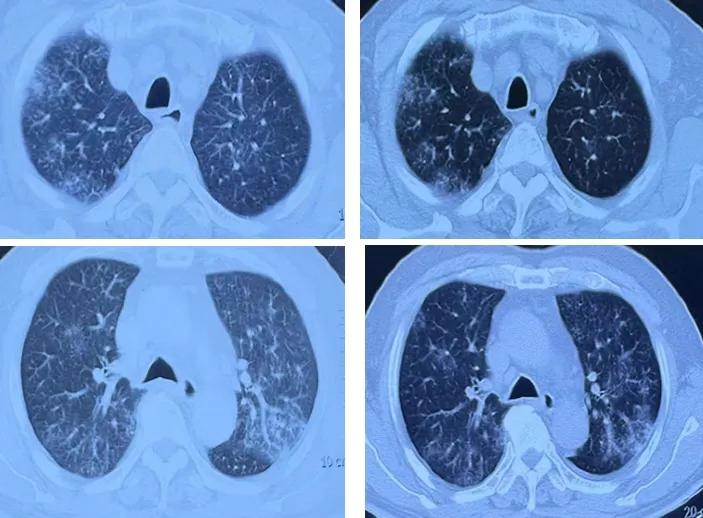

铜绿假单胞菌是一种常见的医院获得性感染病原体 ,但它的表现却常常出人意料。近日,一位65岁男性患者因持续高热、咳嗽和呼吸困难入院。胸部CT显示双肺弥漫性渗出性病变,但常规抗生素治疗效果不佳。更令人困惑的是, 患者痰培养多次提示铜绿假单胞菌 ,但药敏试验显示所有常用抗生素均敏感。